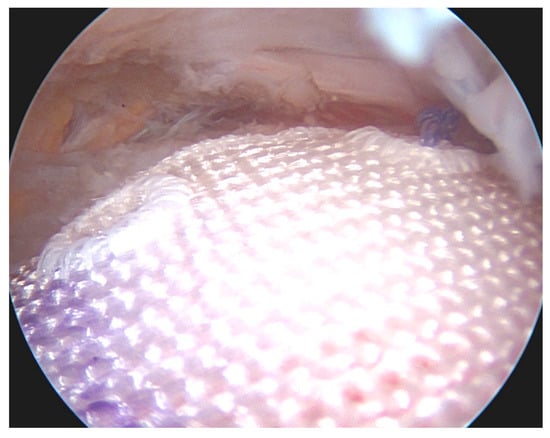

- Patel, A.H.; Savoie, F.H.; O’Brien, M.J. Current concepts and expert practice report: Augmentation of rotator cuff repairs. J. Clin. Orthop. Trauma 2021, 19, 118–124. [Google Scholar] [CrossRef]

- Jung, C.; Spreiter, G.; Audigé, L.; Ferguson, S.J.; Flury, M. Patch-augmented rotator cuff repair: Influence of the patch fixation technique on primary biomechanical stability. Arch. Orthop. Trauma Surg. 2016, 136, 609–616. [Google Scholar] [CrossRef]

- Mehta, V.M.; Mandala, C.L.; Shriver, R.J.; Benson, M. Biomechanical Effects of Fiber Patch Augmentation on Rotator Cuff Repairs. Orthopedics 2020, 43, 42–45. [Google Scholar] [CrossRef] [PubMed]

- Berthold, D.P.; Garvin, P.; Mancini, M.R.; Uyeki, C.L.; LeVasseur, M.R.; Mazzocca, A.D.; Voss, A. Arthroscopic rotator cuff repair with biologically enhanced patch augmentation. Oper. Orthop. Und Traumatol. 2021, 34, 4–12. [Google Scholar] [CrossRef] [PubMed]